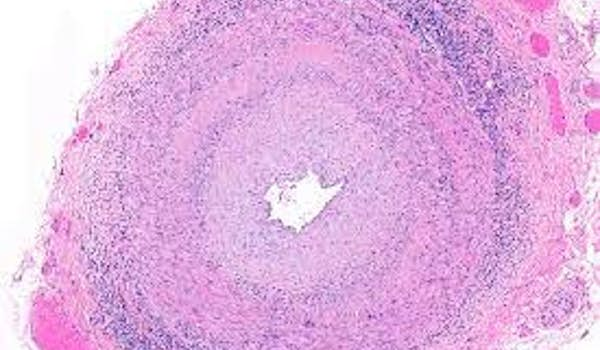

Polyangéite microscopique avec infiltration tubulo-interstitielle par des plasmocytes IgG4

Nous vous invitons à participer à l’étude des patients ayant une polyangéite microscopique avec ANCA anti-MPO et sur l'histologie rénale une importante infiltration tubulo-interstitielle par des cellules inflammatoires composés de plasmocytes IgG4+.